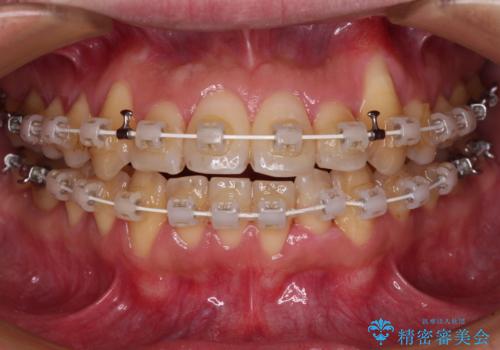

- 矯正装置

- 審美装置

マウスピース矯正での自己管理には自信がないとのことで、ワイヤー装置による矯正治療を行うこととしました。